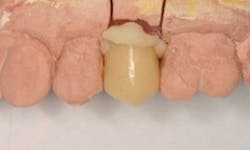

Optimal soft-tissue healing around provisional restorations on teethWhen it comes to implant provisionalization and final restorations, I prefer screw-retained restorations. This does require that implant placement is such that access is through the central fossa of posterior teeth and the cingulum of anterior teeth. Anything near the incisal edge will require either an angulated abutment or a cementable restoration. It’s true that screw-retained restorations do require a little more patience, but it will pay off in spades once you do a few.Here are a few easy steps to make a screw-retained implant provisional restoration that will set the stage for your final crown. This can be done in the mouth for immediate loading situations or after implant uncovering. These techniques can also be done on the bench top after an implant level impression and then delivered to the mouth.1. Place the screw-retained implant cylinder on the implant using the abutment screw.

10. After one to two weeks of tissue healing around the polished provisional, the tissue is shaped and ready for impressions and final restoration.

11. Final restoration in place with well-developed emergence profile and tissue contours.